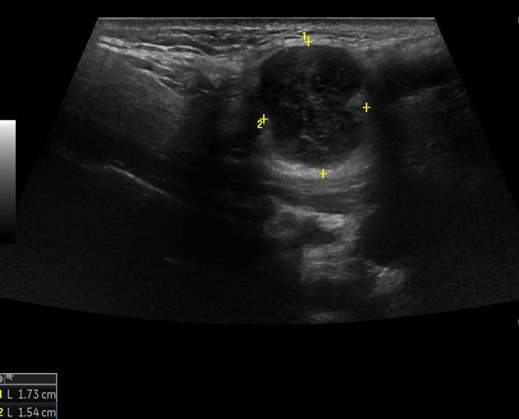

A 69-year-old male noticed a small painless lump in his left parotid region while shaving, Ultrasound examination of the area demonstrated a well-defined lesion measuring approximately 1.7x1.5 cm with internal vascularity, inseparable from the left parotid tail. The rest of the neck ultrasound was unremarkable; MRI was recommended to better define the lesion's origin before histopathological assessment. MRI revealed an oval-shaped, well-defined solid mass lesion in the left parotid gland, measuring about 2.2x1.9x1.3cm in maximum craniocaudally, transverse, and AP dimensions. The lesion is seen as separable from the deep part of the parotid gland, extending posteriorly, abutting the anterior aspect of the related sternomastoid muscle without definite muscle invasion. The lesion eliciting low signal in T1, heterogeneous low signal in T2 weighter images with heterogeneous post contrast enhancement. The main differential diagnoses considered were pleomorphic adenoma and Warthin tumor, although other possibilities could not be totally excluded. Surgical excision was performed. Histopathological analysis revealed Kaposi sarcoma within an intra-parotid lymph node. The lesion was excised with a margin of 0.5 cm. Although the findings were most consistent with a primary nodal Kaposi sarcoma, metastasis from other sites, particularly the skin, should be excluded (Table 1 and Figures 1-4).

Figure 1: Ultrasound of left parotid gland.